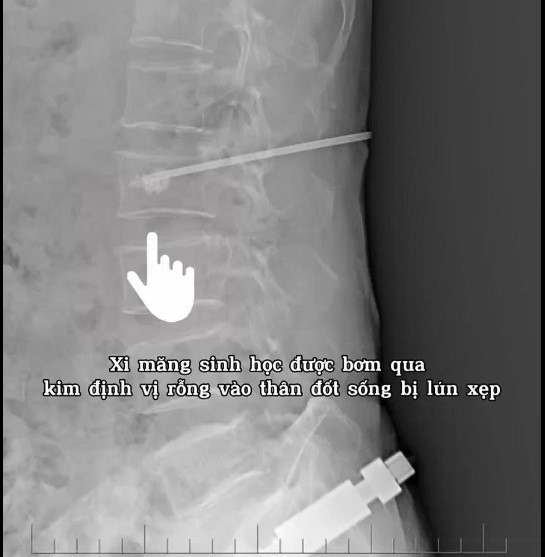

Trước tình trạng trên, người bệnh được hội chẩn chuyên môn và chỉ định phẫu thuật bơm xi măng sinh học tạo hình thân đốt sống L2 nhằm: Giảm đau nhanh chóng; Cố định và tái tạo vững chắc thân đốt sống; Hạn chế biến chứng do nằm lâu; Giúp người bệnh sớm vận động trở lại.

keo-sinh-hoc.jpg

Ảnh BVCC